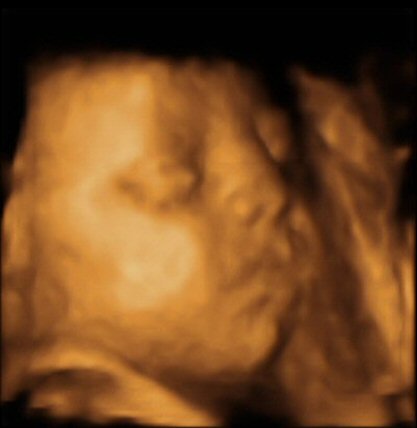

- The scan photos shown below are 3D images from the babybond 4D scan at 29 weeks gestation.